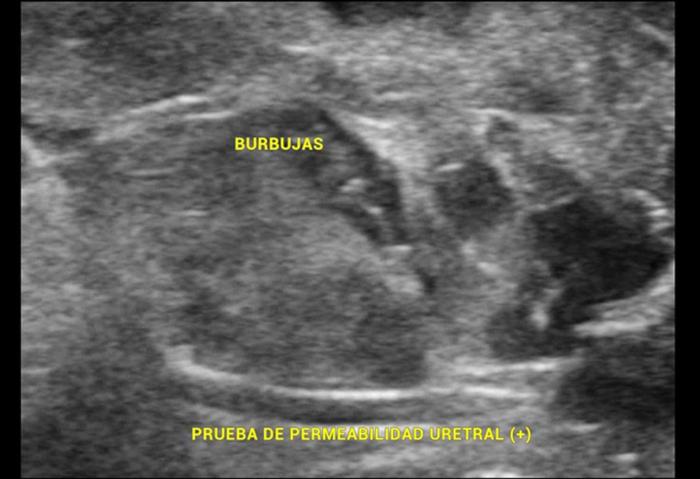

Ultrasonografía con contraste positivo o Prueba de permeabilidad uretral

La técnica descrita se basa en la colocación incompleta de una sonda uretral, es decir, sólo se introduce el extremo de la sonda en la uretra, sin llegar a la vejiga urinaria, y posteriormente se instila una solución salina previamente agitada para generar microburbujas. Ecográficamente, estas burbujas son hiperecogénicas y permiten visualizar, en tiempo real, su salida desde la uretra hacia tejidos adyacentes o la cavidad pélvica, confirmando la ruptura uretral.

Esta evaluación diagnóstica también es conocida como “Prueba de permeabilidad uretral”.

- Las microburbujas introducidas permanecen en suspensión escasos segundos, por lo cual se sugiere la observación por ultrasonido sincrónica, es decir, intentar ver a las burbujas mientras van saliendo de la sección uretral afectada.

- En pocos segundos las microburbujas se reunirán formando una gran burbuja. La reverberancia de dicho gas acumulado impedirá la correcta evaluación de la zona, por lo cual se sugiere realizar la prueba de permeabilidad uretral luego de haber revisado la zona por completo.

Mediante el estudio ultrasonográfico se detectó la presencia de líquido acumulado en la cavidad pélvica, en la zona peri-uretral, con esteatitis asociada (Figura 5). Debido a estos hallazgos se sospechó una ruptura traumática de la uretra, por lo cual se sometió a la paciente a una prueba de contraste uretral positivo, la cual evidenció la perforación uretral (Figura 6).

Luego de un corto tiempo, el aire introducido se acumula en el subcutáneo (Figura 7) (Vídeo 2).